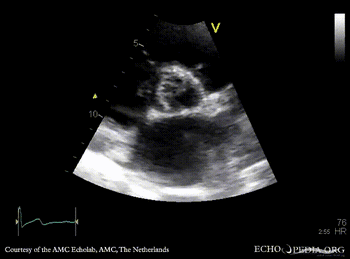

PSAX: thickend aortic valve M-Mode: dilated left ventricle